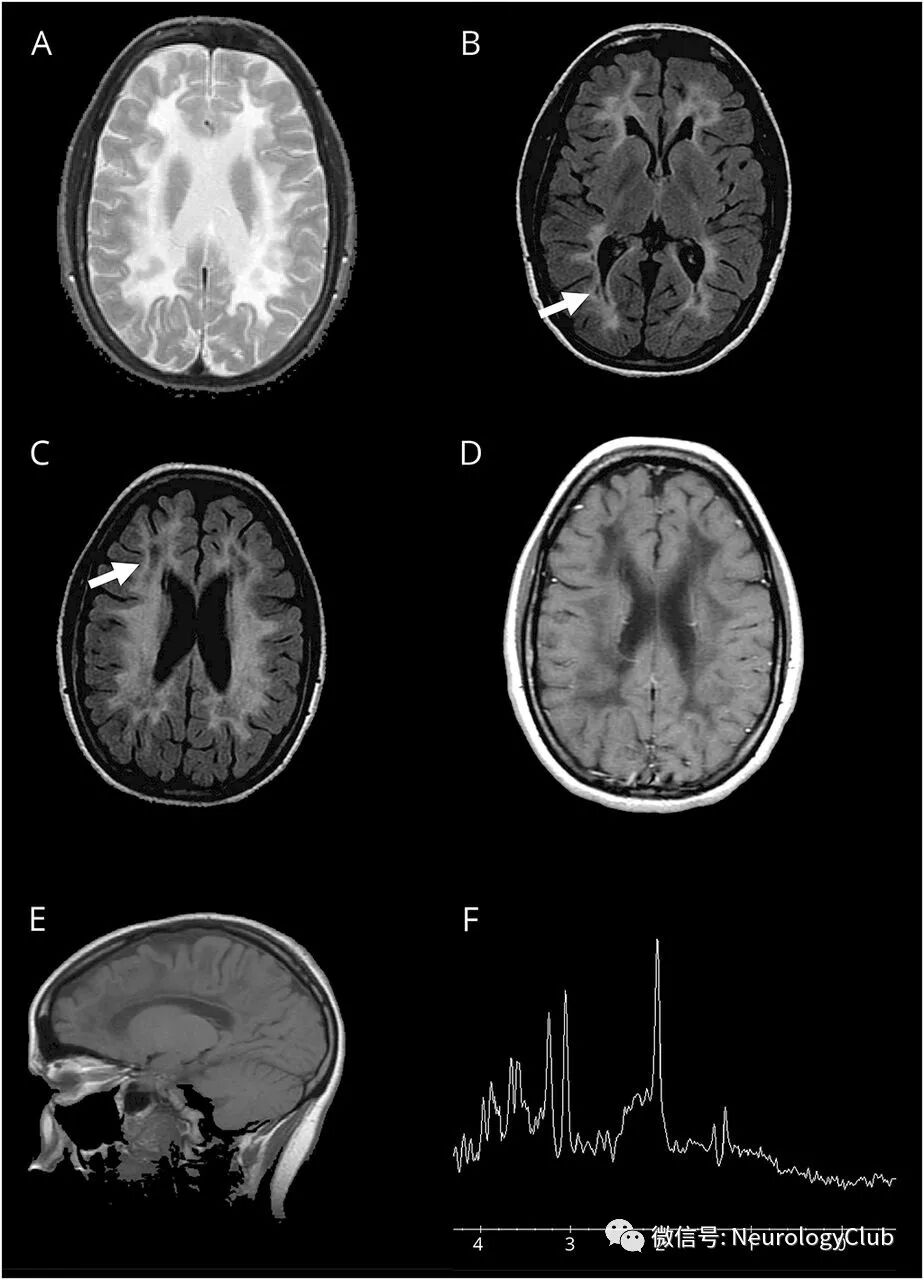

18岁卵巢早衰女性患者,在病毒感染后2周出现局灶性运动性癫痫发作并继发全面性发作和头痛。她最近有精神压力。查体仅发现全身反射亢进。神经影像学提示双侧融合性白质病变和脑室周围囊性变(图)。

(图:A:T2WI可见广泛性脑白质病变;B-C:FLAIR可见脑白质弥漫性异常,伴部分囊性变[箭];D:增强T1未见病灶强化;E:矢状位T1WI可见白质异常信号和胼胝体变薄;F:磁共振波谱可见乳酸峰轻度升高)